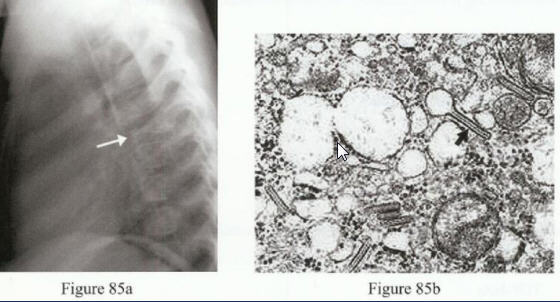

What is the structure

outlined by the black arrow in Figure 85b?

Birbeck granules (diagnostic of LCH)

LCH is also confirmed by CD1a

immunohistochemical staining.